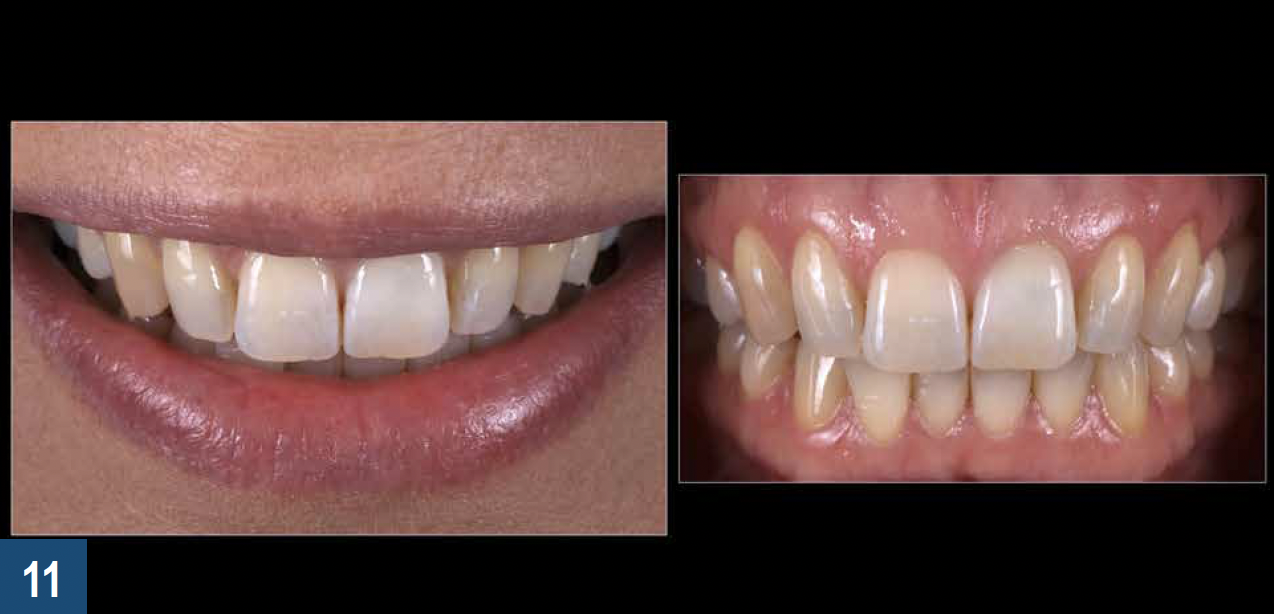

For clinical situations involving a nonvital and discolored natural tooth (Figure 10), intracoronal bleaching, also known as the "walking bleach" technique, has been consistently shown to be a conservative treatment option compared with more aggressive direct/indirect restorative procedures such as composite bonding, porcelain laminate veneers, or full coverage crowns.33Additionally, for patients requesting the lightening of a single dark tooth, internal bleaching is often more cost-effective and less dependent on patient compliance than the daily use of a whitening tray. Contemporary protocols often include the use of strong oxygen-releasing chemical compounds, such as 30% to 35% hydrogen peroxide, which have been associated with adverse complications including external invasive cervical root resorption.34,35 The evaluation and outcomes of endodontic techniques utilizing a safer 10% carbamide peroxide formulation are well-documented in the literature and clinically, and have proved to be a reliable, predictable option for the internal bleaching of nonvital discolored teeth (Figure 11).36-38

Fig 11. Left panel: The final esthetic results after 1 week of nonvital intracoronal bleaching (the “walking bleach” technique) and a 2-week color stabilization phase. Right panel: Occasionally the discolored tooth may appear slightly whiter than the adjacent teeth in retracted photos following internal bleaching; however, this situation is rarely objectionable to the patient and may prompt a request to bleach their remaining teeth.